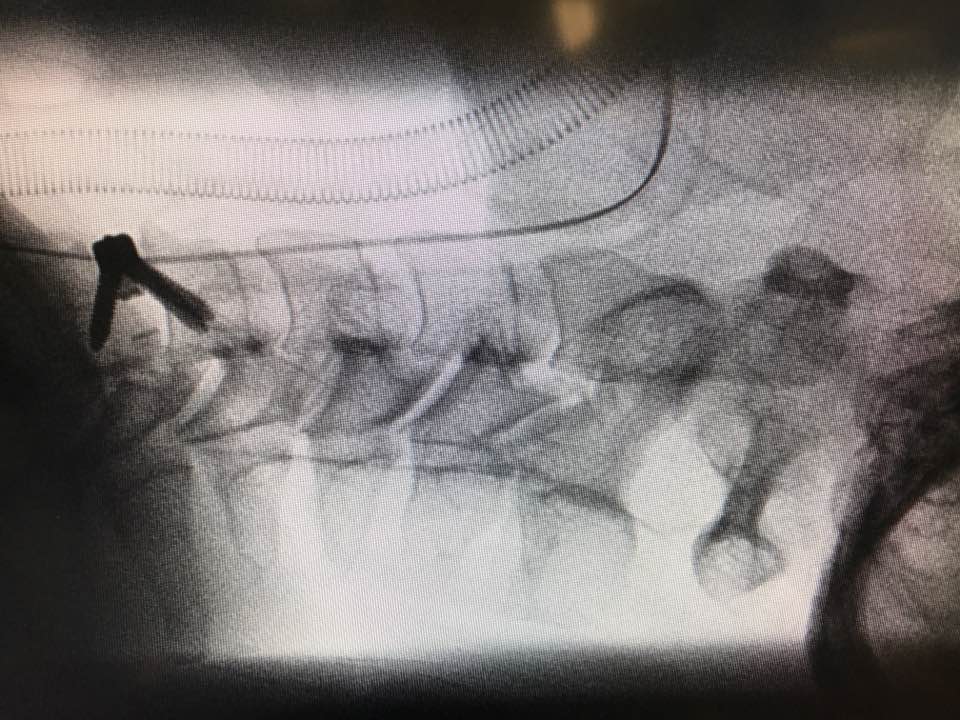

前路颈椎间盘切除及椎间融合和脊髓神经减压手术(ACDF)

手臂因椎间盘突出,压迫脊髓神经而无力

刚刚完成,又是在星期日的手术